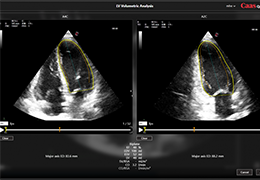

High-quality and fast 3D reconstruction and 3D rendering

Performs 3D reconstruction and volume rendering.

Side-by-side comparative assessment for pre- and post-operative scans.